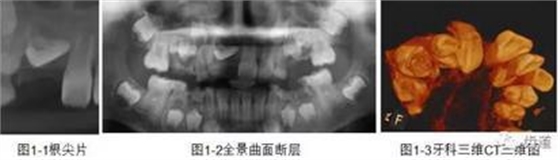

CBCT在牙體牙髓病科治療中,對牙根周圍的解剖關(guān)系、炎癥病變、囊腫等就能夠輕而易舉的進(jìn)行診斷。甚至與牙齒內(nèi)根管的數(shù)目、走向、分支等都能夠通過牙科CT進(jìn)行展示,使臨床醫(yī)生的根管治療不再是完全憑手感的“經(jīng)驗(yàn)科學(xué)”。通過CBCT,還可以對一些“久治不愈“的疑難病例進(jìn)行檢查和診斷,例如根縱列的診斷、根管內(nèi)異物的定位等,找準(zhǔn)了原因,結(jié)合先進(jìn)的治療技術(shù)因病施治,使疑難病例的治療變的輕松起來。

1、牙髓根管治療

1)根管治療中牙膠尖充填在CBCT中的影像

2)根管測量

2、多生牙

多生牙的定位